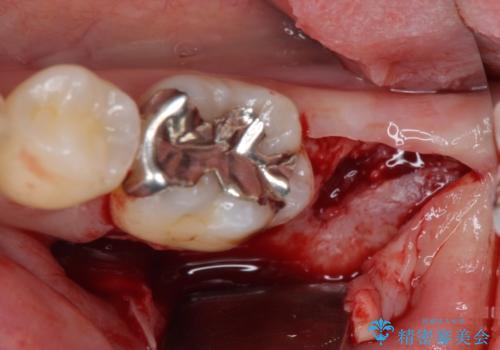

- 左下の奥歯に違和感を感じて来院された患者様です。

診察をした結果、歯根にまで及んだ虫歯と歯周病による著しい骨欠損が認められ、抜歯をせざるを得ない状況でした。